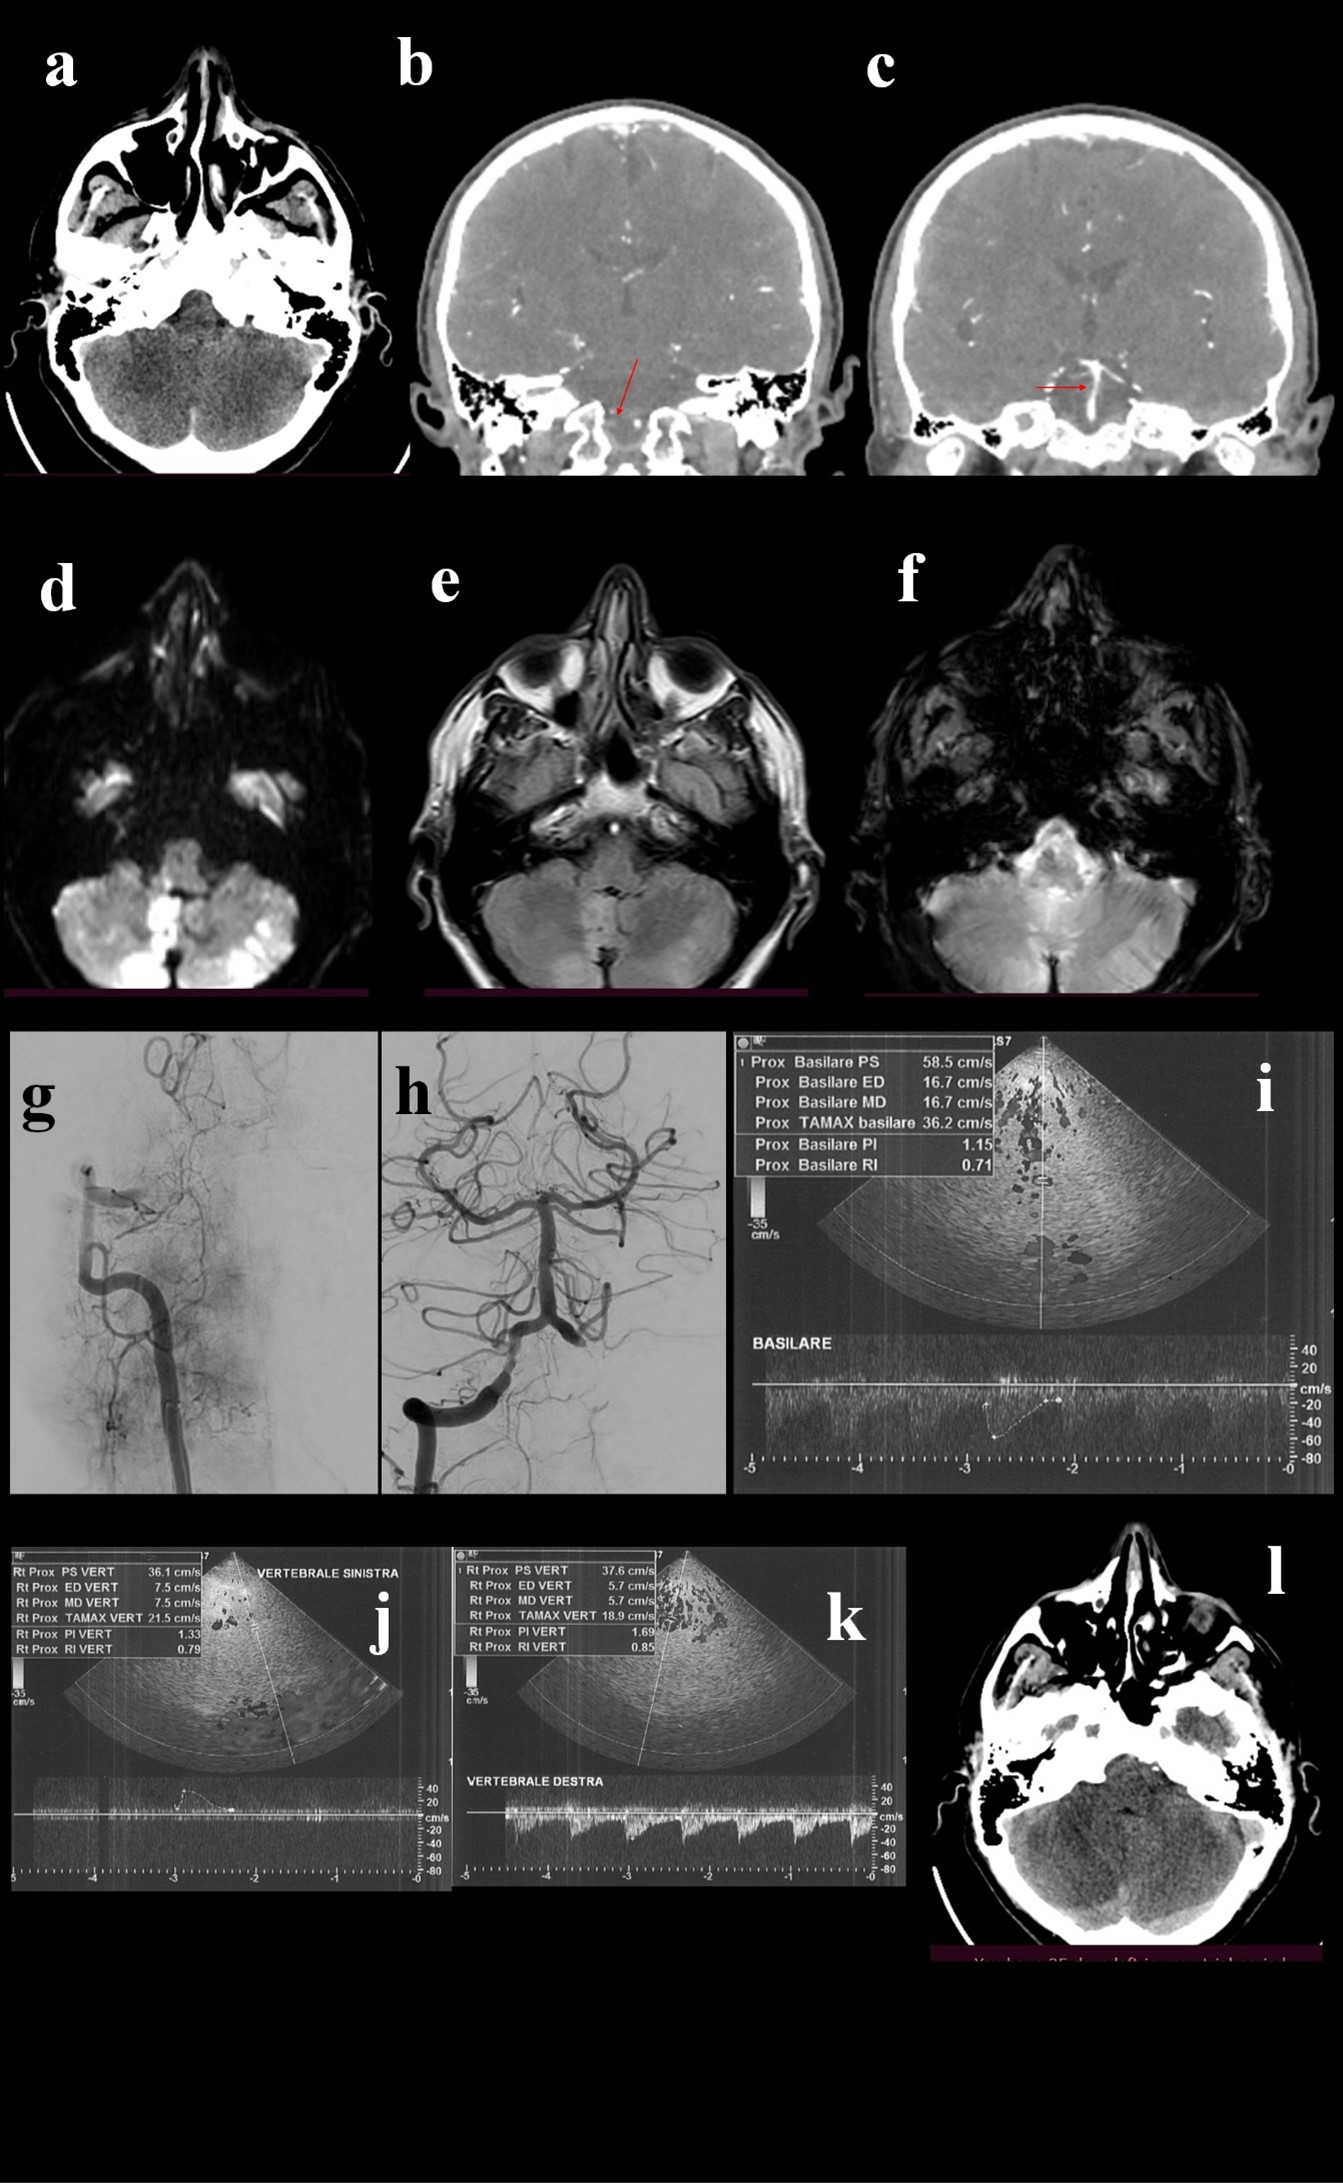

Figure 1. A 58 year old male patient, with history of smoking and hypertension, was urgently admitted for wake-up stroke, characterized by vertigo, vomit, diplopia, ataxia and progressive alteration of mental status. Head CT (a) scan did not detected acute lesions, CTA showed occlusion of V4 tract of right vertebral artery (b, arrow) with stenotic extension to the basilar artery (c, arrow). Urgent MRI showed bilateral cerebellar and bulbar DWI hyperintensities (d), less evident in FLAIR sequences (e) and with no hypointensities in GE sequences (f). DSA confirmed V4 occlusion of right vertebral artery (g), that was treated with mechanical thrombectomy. The final angiogram showed post-procedural right V4 and basilar stenosis (h). Given the risks of the complex stenting of both arteries, VB hemodynamics were analyzed by TCCS, that showed diffuse angiosclerotic flow without significant focal alterations (i, j, k). Based on these findings stenting was not performed. The patients slightly improved and 24-hours control brain CT scan (l) did not point out a limited right cerebellar hypointensity.